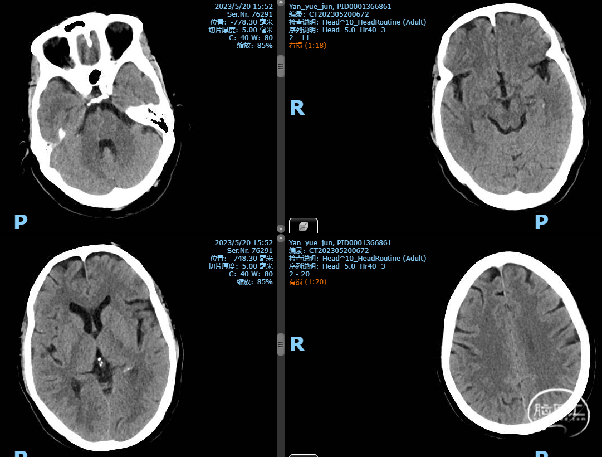

一般项目:姓名:闫月君 性别:女 年龄:64,因“右侧颈内动脉动脉瘤栓塞后半年”于2023-5-15 11:59 非急诊入院。

患者自诉半年前在广西壮族自治区人民医院桃源区行右侧颈内动脉C6动脉瘤血流导向密网支架(Pipeline)植入术,术后病情好转出院,现为复查造影入院。

诊断:1、左侧颈内动脉C6段动脉瘤 2、右侧颈内动脉C6段动脉瘤血流导向密网支架植入术后

2023-5-19手术

右侧ICA造影:动脉瘤正处于继续愈合状态,无需再处理

左侧C6多发动脉瘤

术后第一天